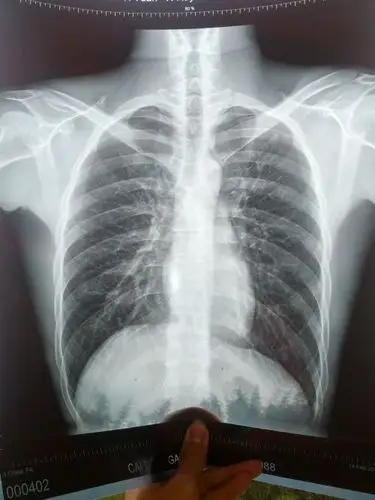

邝伯的胸片显示假牙掉落在支气管内